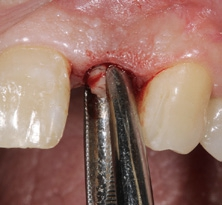

Der chirurgische Eingriff wurde unter Lokalanästhesie mit palatinaler und labialer Infiltration durchgeführt. Zuerst erfolgte die Entfernung des Implantats. Für die Explantation wählten wir das aus unserer Sicht knochenschonendste Verfahren. Mithilfe einer Extraktionszange und mit entsprechend dosierter Kraft drehten wir das teilweise ankylotische Implantat in Achsrichtung aus, um auf jeden Fall die dünne labiale Knochenlamelle zu erhalten (Abb. 3). Dabei frakturierte der osseointegrierte Implantatapex tief im Implantatbett (Abb. 4). Um diesen zu entfernen, musste ein minimalinvasiver apikaler Zugang geschaffen werden. Nach einer krestalen Inzision mit mesialer Tunnelpräparation und distaler Entlastungsinzision sowie der Präparation eines Mukoperiostlappens zeigte sich ein ausgeprägter konkaver Alveolarknochen. Mit einem piezotechnisch unterstützten Chirurgieansatz fenestrierten wir die labiale Knochenlamelle (Abb. 5). Durch diesen minimalinvasiven Zugang lösten wir die ankylotische Verbindung und entfernten den apikalen Implantatrest. Bei dieser Methode der Implantatentfernung wird der periimplantäre krestale Knochen weitestgehend geschont.